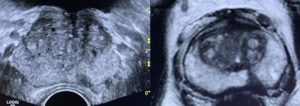

Biópsia Próstata